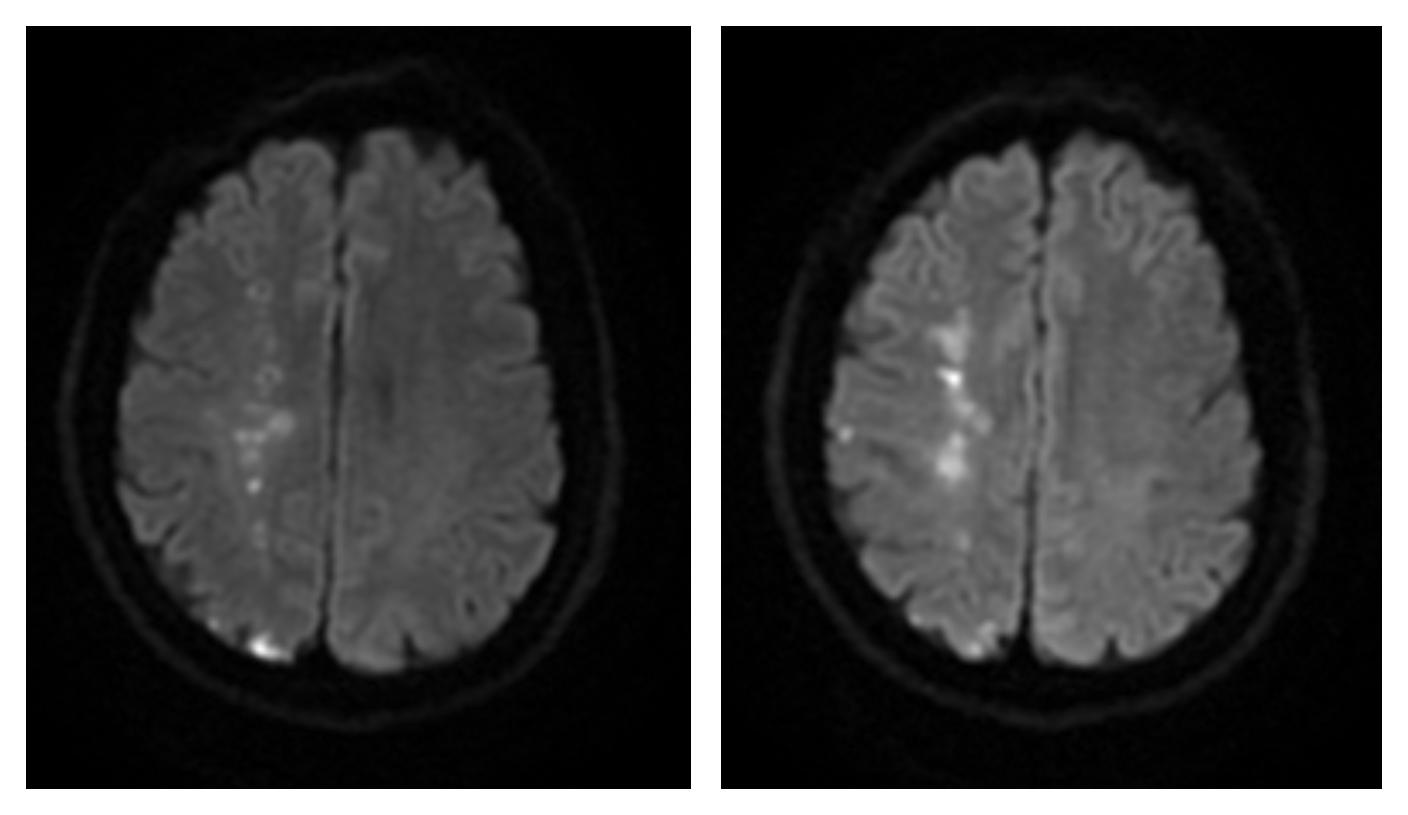

56岁男患,因“左侧肢体无力2月余”入院;既往有高血压病史,规律口服药物治疗。查颅脑MRI+DWI提示右侧额颞顶枕叶散在多发急性脑梗死;查头颈部CTA提示右侧颈内动脉C1段混合斑块,官腔重度狭窄;查头颅CTP提示右侧基底节区、额叶、颞叶、顶叶、枕叶异常灌注区,积极行右侧颈内动脉起始段球囊扩张形成术及支架植入术,再配合康复治疗,最终恢复正常出院。

术前影像DWI